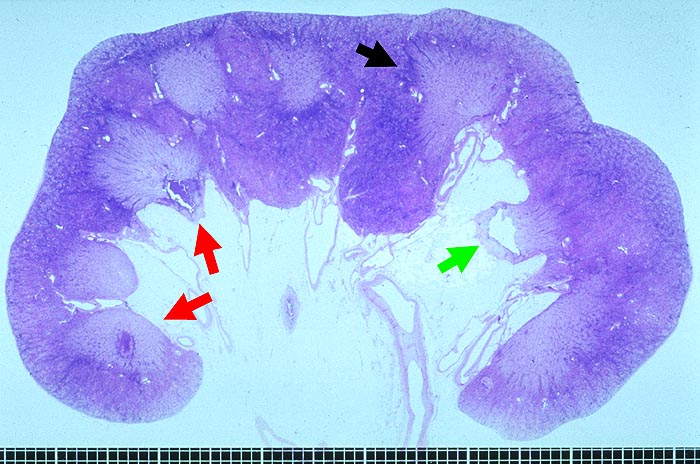

PathoPic – image database / PathoPic ID 1625 - Papillennekrosen bei Analgetikanephropathie

Papillennekrosen bei Analgetikanephropathie

Sämtliche Papillen sind ► nekrotisch. Eine einzelne ► Papillenspitze ist bereits abgestossen. Aussen sind die Papillennekrosen von einem ► Infiltratmantel umgeben.